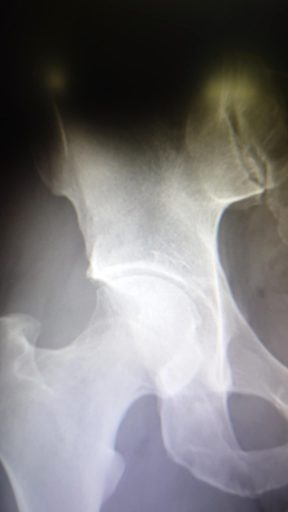

股関節の 定点診察をしに行きました

腰痛も無し

まったく問題なし

リハビリまだまだ続けてねと

左も唇損傷になる可能性があるから気を付けてねとも

お願いして撮影してもらいました

左右のクリート位置が違うのが納得できました